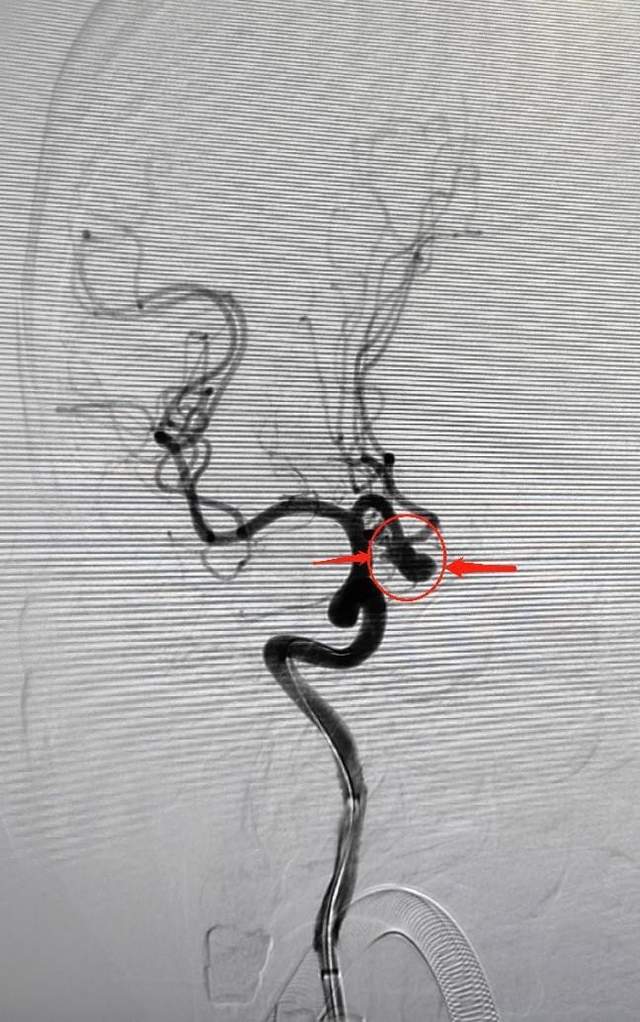

术后图片

术后动脉瘤腔造影剂滞留明显,子囊未显影,颅内血管通畅。